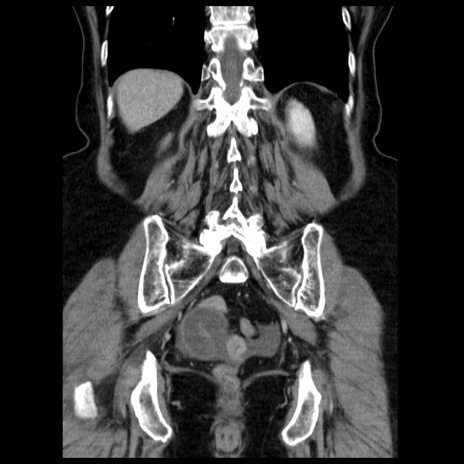

症例13(冠状断像)

【症例】70歳代女性

【主訴】腹痛、嘔吐

【現病歴】15時間程前(昨晩)より腹痛あり。今朝になっても症状の改善なく、嘔吐あり。腹痛も増悪あり、救急外来受診。

【既往歴】子宮癌全摘術後

【身体所見】意識清明、BP 121/72mmHg、P 74bpm、SpO2 100%(RA)、腹部:平坦・軟、腸雑音ほぼ聴取せず。下腹部・心窩部・臍左上に圧痛あり。反跳痛なし。

【データ】WBC 10600、CRP 0.15